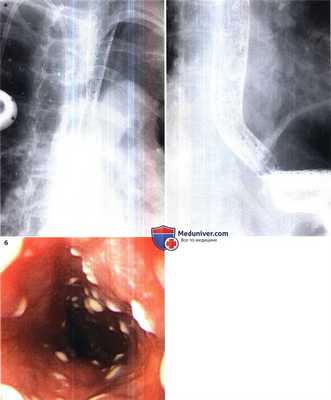

(Слева) На аксиальной КТ с контрастным усилением, выполненной пожилому мужчине с выявленным ранее раком легкого, у которого появилась дисфагия и боль при глотании в течение курса лучевой терапии на область средостения, определяется опухоль правого легкого и медиастинальная лимфаденопатия. Стенка пищевода утолщена, просвет его сужен.

(Справа) На рентгенограмме пищевода у этого же пациента определяется протяженная стриктура средних отделов грудного сегмента пищевода с расширением его проксимальной части, что отражает частичную обструкцию в этом «классическом» примере лучевого эзофагита. (Слева) На аксиальной КТ с контрастным усилением, выполненной мужчине среднего возраста с известным раком легкого, получавшего лучевую и химиотерапию, определяется выраженный фиброз и уменьшение объема правого легкого в отделах, прилежащих к средостению в области облучения.

(Справа) На рентгенограмме пищевода с бариевой взвесью у этого же пациента визуализируется протяженная, выраженная стриктура верхних и средних отделов пищевода в зоне облучения. Глотка над областью сужения просвета пищевода расширена.